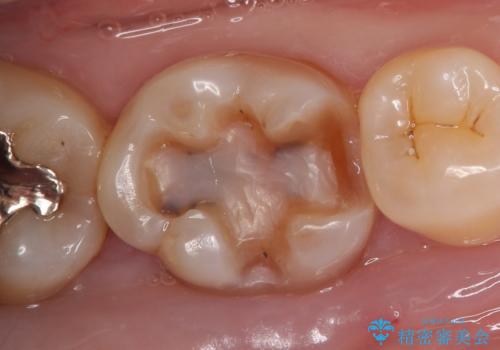

- 右下6番目の歯の舌側に虫歯があるので治療して欲しいといらっしゃった方の症例です。

古い銀歯及び虫歯を除去後、セラミックインレーにて修復を行いました。